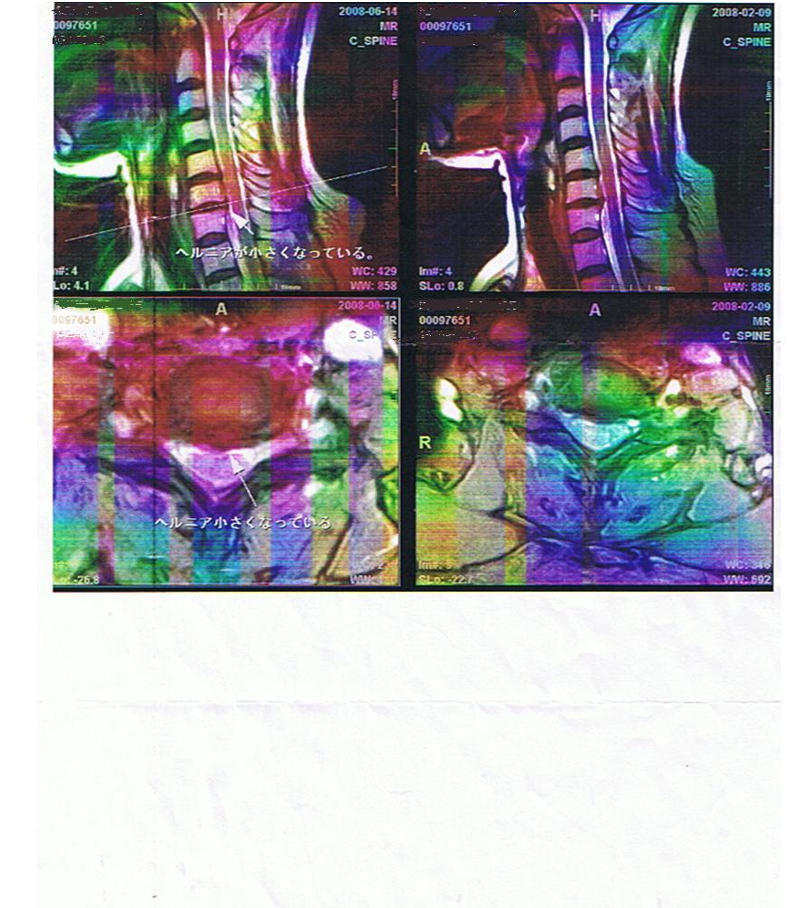

54歳 女 頚椎椎間板ヘルニア パート